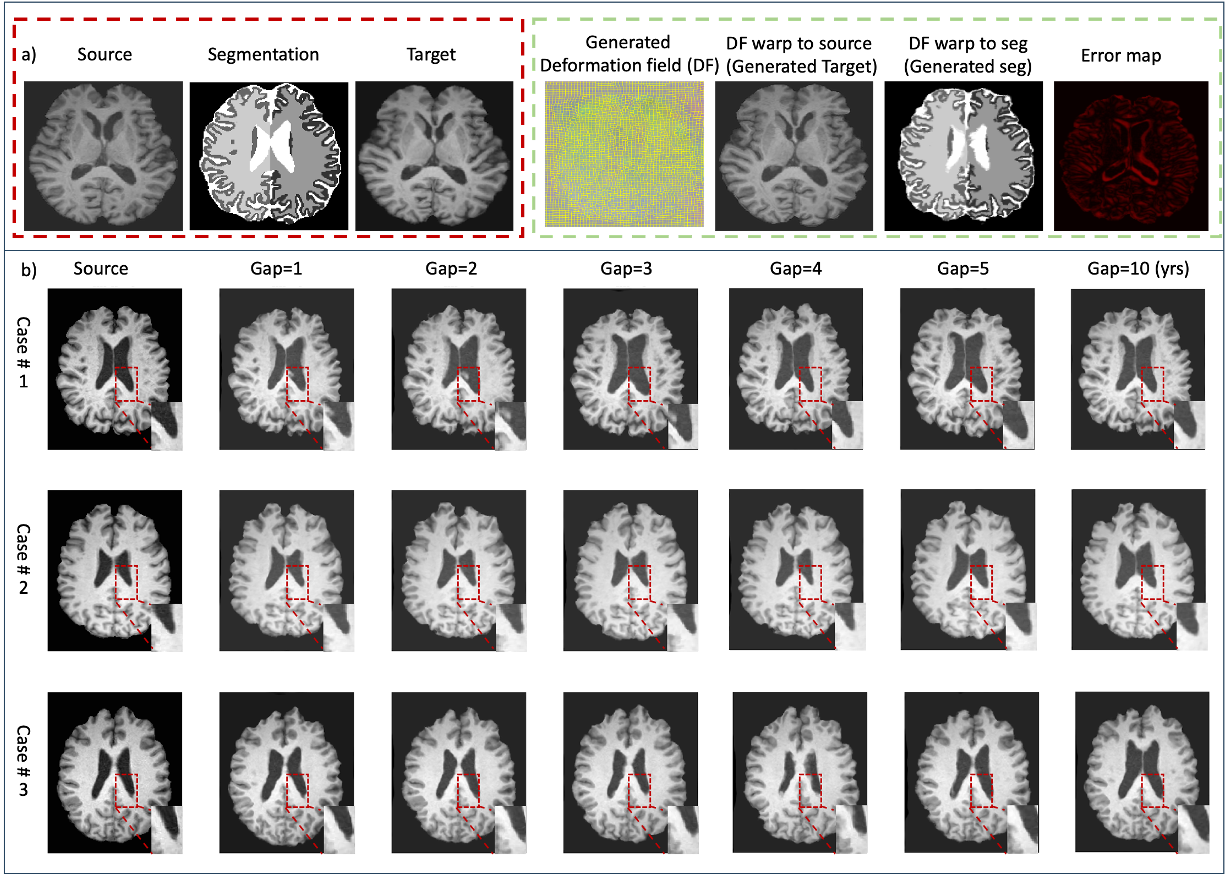

Qualitative Results: As shown in Fig. 2, our method generates realistic aging patterns. For instance, when generating a 70-year-old brain from a 60-year-old source, the model produces plausible ventricular enlargement. The intrinsic modality-agnosticism is demonstrated by applying the same deformation field to both a T1w image and its segmentation map, yielding a consistent pair of future data points. Our model also captures complex, non-linear aging trajectories observed in real data. For instance, the apparent ventricular shrinkage in some 2D slices (as seen in some examples) can reflect non-monotonic volume changes over time or be an artifact of slice selection through a 3D structure that is globally, but not uniformly, expanding.

Refer to caption

Figure 2: (a) Our method generates a deformation field (DF) to warp a source image (age 60) and its segmentation map to a target age (70). The generated images show plausible aging effects like ventricular enlargement. (b) Examples of longitudinal generation with increasing age gaps, demonstrating the model’s ability to capture progressive and anatomically consistent changes, such as the gradual expansion of ventricles over time.